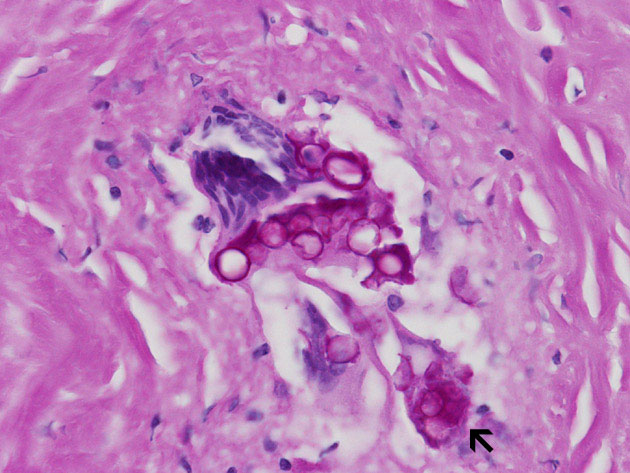

Hematoxylin & eosin

Area 2: The granulomas are composed of histiocytes in concentric arrangements forming nodules. At the center of the granulomas are mulitnucleated ginat cells containing the fungus.

• The spheres of Coccidioides are among the largest that are seen in histologic sections and range from 30 to 60 μm. Most of the fungal organisms are likely to be non-viable in this case because of aggressive fungal therapy. The impressive foreign body type giant cell reaction is likely a reaction to the non-viable spores.